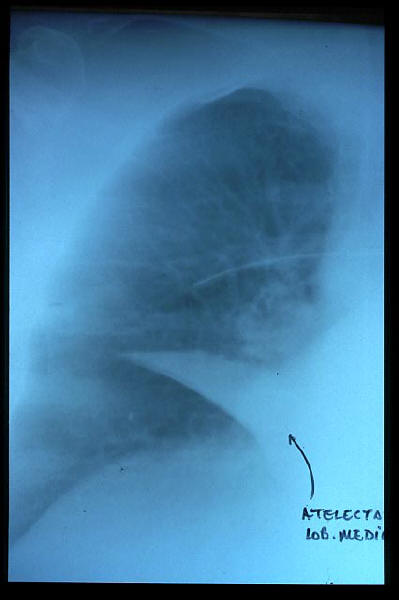

Atelectasia lóbulo medio.